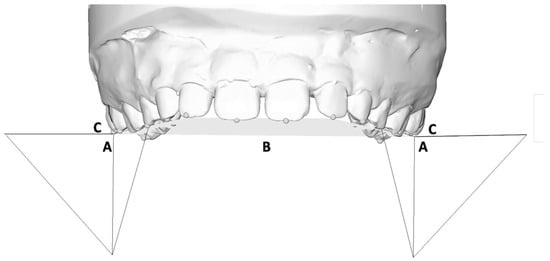

2.2. Measurement Protocol

- Inter-canine width: linear distance between cusp tips of the deciduous canines (A);

- First inter-deciduous molar width: linear distance between the vestibular cusp tips of the first deciduous molars (B);

- Second inter-deciduous molar width: linear distance between the sulcus of the second deciduous molars (C);

- First inter-molar mesial width: linear distance between the mesiobuccal cusp tips of the first molars (D);

- First inter-molar distal width: linear distance between the distobuccal cusp tips of the first molars (E);

- First inter-molar transpalatal width: linear distance between the groove of the first molars at the mucosa (F);

- Inter-canine transpalatal width: linear distance between the groove of the deciduous canines at the mucosa (A’);

- First inter-deciduous molar transpalatal width: linear distance between the groove of the first deciduous molars at the mucosa (B’);

- Second inter-deciduous molar transpalatal width: linear distance between the groove of the second deciduous molars at the mucosa (C’).